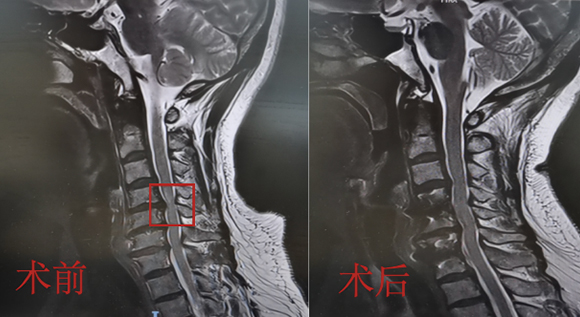

脊柱脊髓神经微创中心以微创技术为引领,以功能恢复为目标,主要治疗脊柱外伤、肿瘤、退行性病变、脊柱畸形等疾病。团队利用神经外科显微技术,结合神经内镜微创技术,对脊柱间盘变性疾病、颈腰椎管狭窄、颈腰椎间孔狭窄、颈腰椎间盘突出、颈腰椎体不稳、脊柱骨折、寰枢椎脱位、脊柱肿瘤、椎管内肿瘤、脊髓损伤、脊髓空洞、脊髓栓系等疾病进行高效、特色手术治疗,如颅颈交界区畸形寰枕减压内固定术、脊柱肿瘤全脊椎切除内固定术、微创椎管内肿瘤切除术、微创脊柱旁肿瘤切除术、寰枢椎脱位椎间融合内固定术、脊柱骨折微创经皮椎弓根钉内固定术、经椎间孔椎间融合内固定术(MIS—TLIF)等,最大程度降低脊柱脊髓手术创伤,具有创伤小、输血少、恢复快、口碑好,出院早等优势。

• 1椎管扩大成形术

• 2脊柱肿瘤全脊椎切除内固定术

• 3微创椎管内肿物切除术

• 寰枢椎脱位椎间融合内固定术 4

• 5脊柱骨折+腰椎滑脱-椎弓根钉内固定术

• 颈椎间盘切除、椎管减压术 6